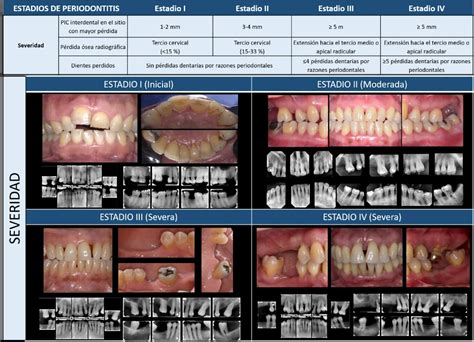

Los pacientes con periodontitis estadio IV se enfrentan a desafíos complejos que requieren un tratamiento interdisciplinario para restaurar la salud y la función oral; en este ámbito, los implantes han ampliado las opciones de tratamiento, demostrando una alta tasa de supervivencia. La evaluación clínica en periodontitis estadio IV es compleja y requiere un diagnóstico específico y, para ello, resulta especialmente útil la clasificación mundial de las enfermedades periodontales y periimplantarias de 2018.